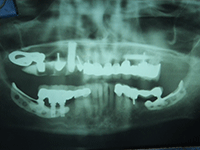

| Figure 1: Subperiosteal design dental implants | ||

Commercial dental implants came to the United States in 1940 with Gustavo Dahl presenting the first dental implants—a subperiosteal design (Figure 1). Dental implants have undergone various transformations in design, shape architecture, and metallurgy or component constituency. Currently, hundreds of different designs and components exist. Since their inception in 1940, implants have changed from the subperiosteal design to blade-type or endosteal implants invented by Dr. Leonard Linkow of New York (Figure 2), to modern screw-type implants (Figure 3) and mini implants (Figure 4), with each type promoting different restorative options in the field of dental implantology. All of these, when located in unknown remains, can provide a useful tool for the forensic dentist as a possible piece of the puzzle in the identification protocol.